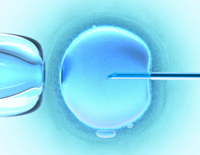

Mesterséges megtermékenyítés- IVF

Magyarországon 100-150 ezer embert érint a terméketlenség. Meddőségről akkor beszélünk, ha egy pár 1 éve védekezés nélkül él nemi életet és terhesség mégsem következik be. Az első sikertelen év elteltével érdemes szakemberhez... »